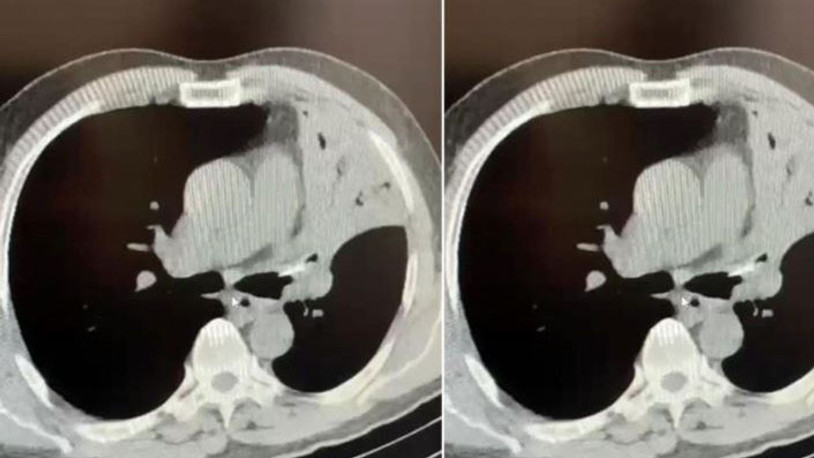

Öksürük şikayetiyle gittiği hastanede 5 yıldır akciğerinde lades kemiğiyle yaşadığını öğrendi.

Bolu’da öksürük ve şiddetli ağrı şikayetiyle gittiği hastanede 5 yıldır sol akciğerine saplanan lades kemiğiyle yaşadığını öğrenen Mehmet Salih Fer, kemiğin ameliyatla alınması sonucu sağlığına kavuştu.

Edinilen bilgiye göre, Düzce’nin Cumayeri ilçesinde yaşayan Mehmet Salih Fer, uzun süredir devam eden öksürük ve şiddetli ağrı şikayetiyle AİBÜ İzzet Baysal Eğitim ve Araştırma Hastanesi’ne gitti. Fer’in yapılan muayenesinde sol akciğerine lades kemiği saplandığı tespit edildi. Fer’in 5 yıl boyunca akciğerinde saplanmış halde bulunan lades kemiği yapılan ameliyatla alındı. Sağlığına kavuşan Fer, yapılan son kontrollerinin ardından taburcu edildi.

5 yıl boyunca öksürük, şiddetli ağrı sırtında yanma şikayetleri bulunduğunu ifade eden Mehmet Salih Fer, “Aynı şikayetlerle hastanelere gittim, muayenelerim yapıldı, filmler çekildi. Sık sık enfeksiyon geçiriyordum, farklı farklı tanılar konuldu ve ilaç tedavileri başlatıldı. Ancak hiçbir sonuç alamadım ve şikayetlerim devam etti. Son olarak İzzet Baysal Eğitim ve Araştırma Hastanesi Göğüs Cerrahisi kliniğine geldim. Burada doktorlarım tarafından muayenelerim ve tetkik işlemlerim yapıldı. Neticede sol akciğerimde yaklaşık 5 senedir bir lades kemiği ile yaşadığımı öğrendim” dedi.